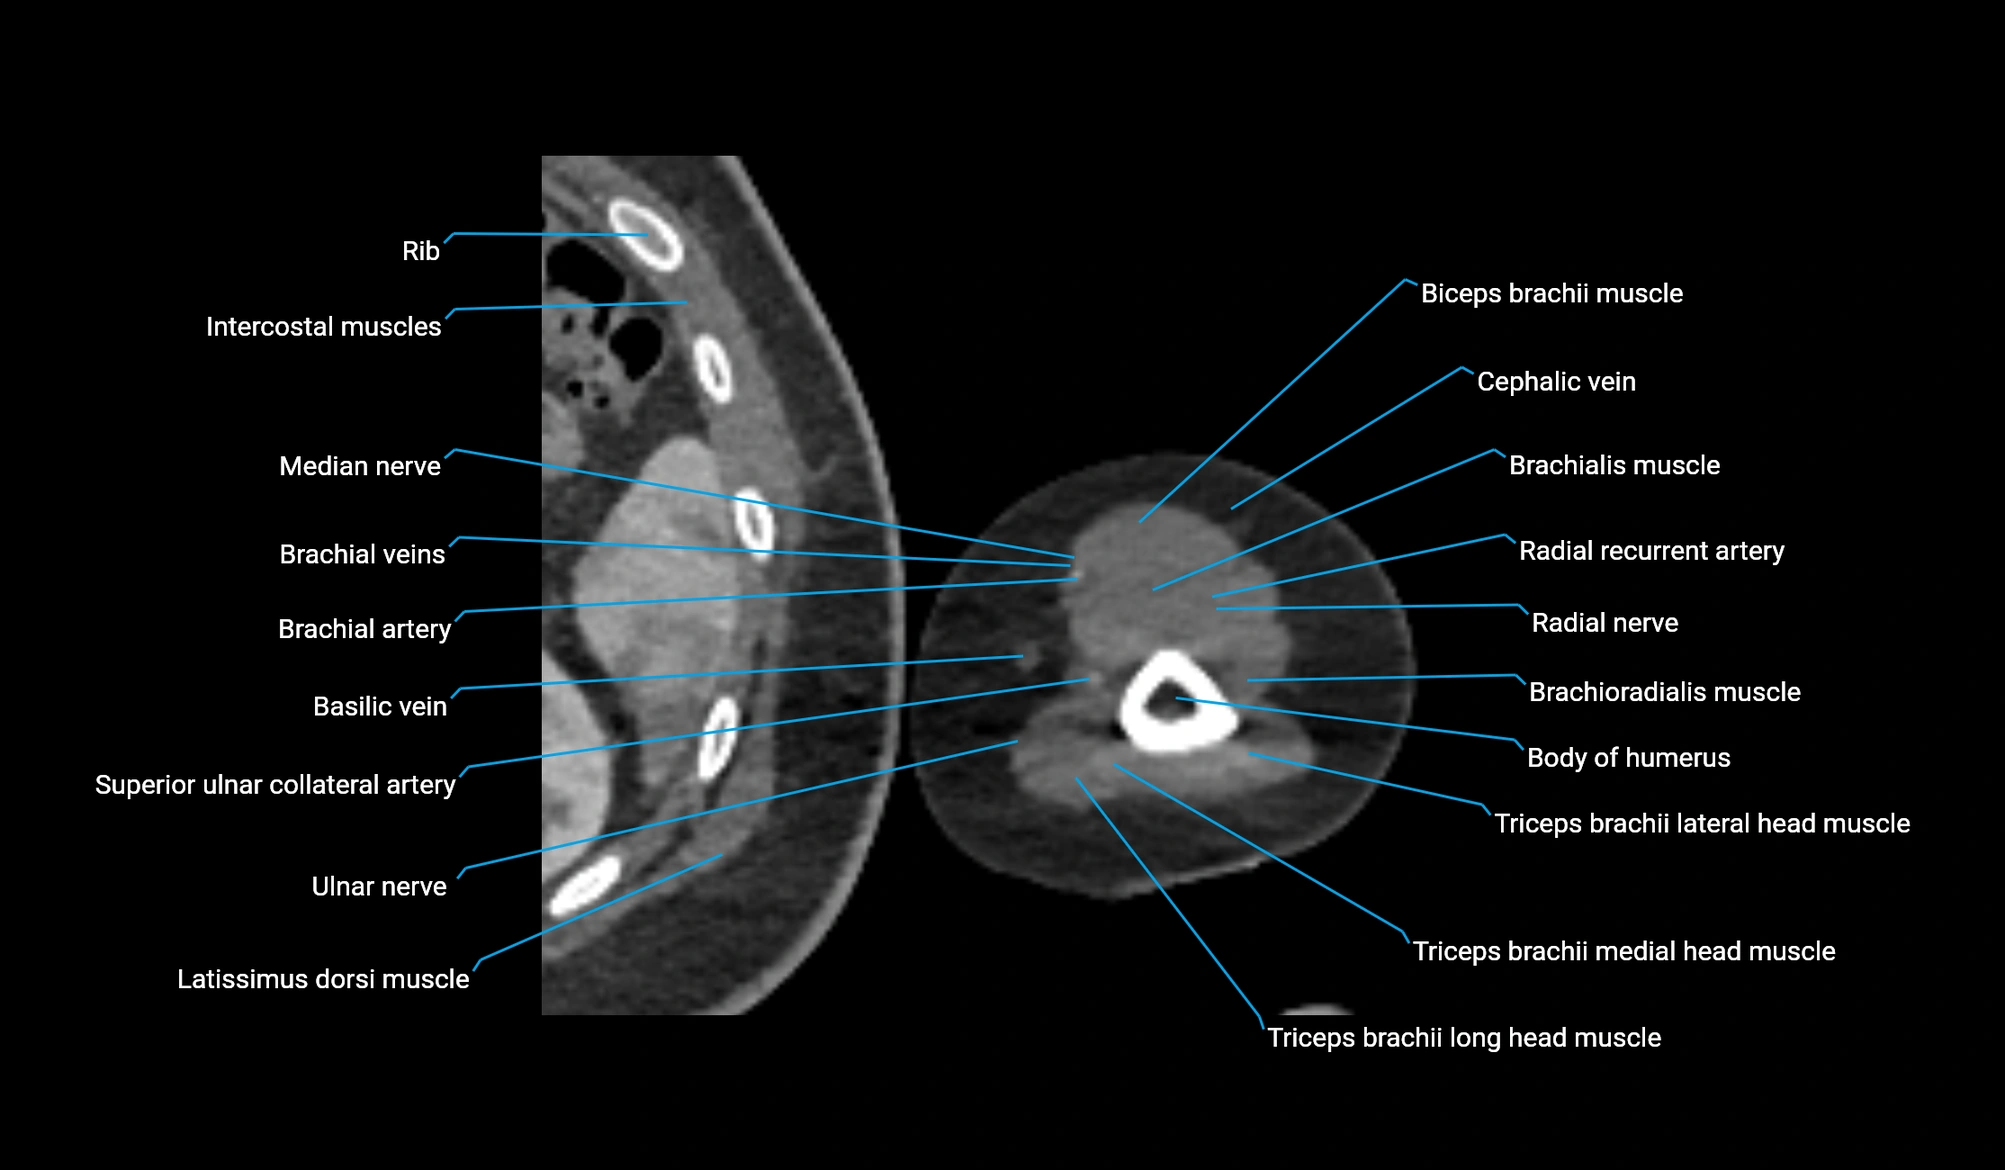

MRI image

CT image